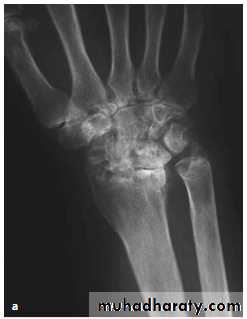

Lateral radiograph

Radiological evaluation